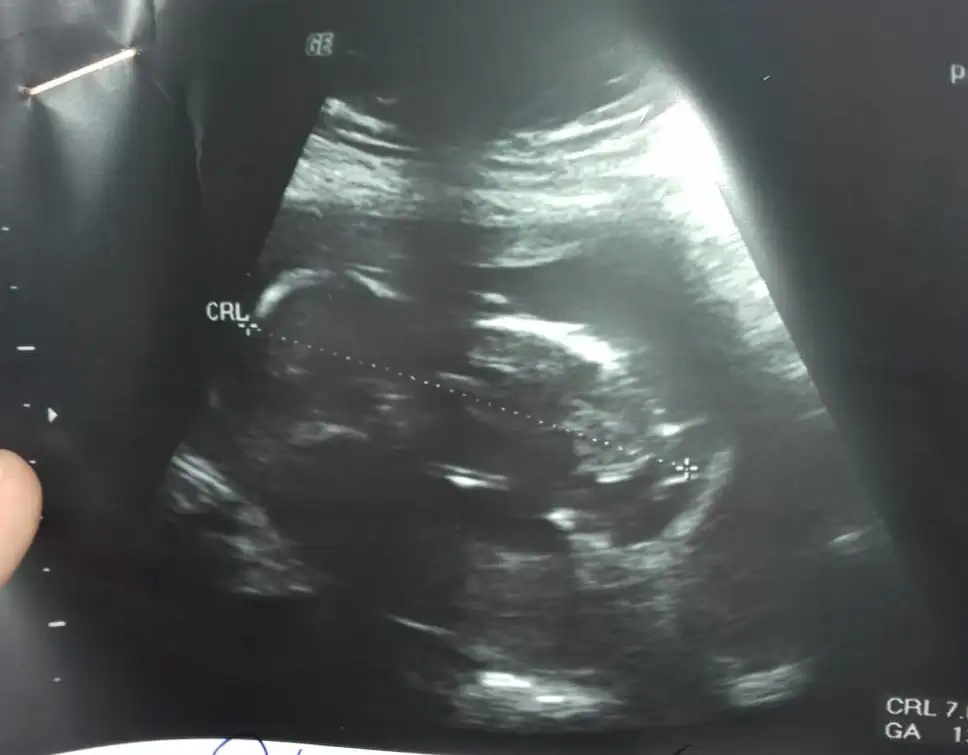

Bana da tahmin de buluabilir misiniz? :KK36: daha küçük ama